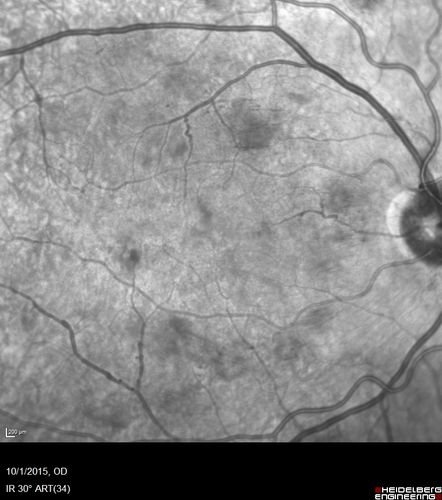

Hairy Cell Leukemia - Retinal Hemorrhage and twig Branch Vein Occlusion

79 year old man He has had hairy cell leukemia since 2002.  He is in remission.  His last blood tests were 9/2018.  He just moved down here and needs a new leukemia doctor.  His vision is fine.

VA OD: Dcc20/25

VA OS: Dcc20/25

IOP: TP: OD:12 OS:12